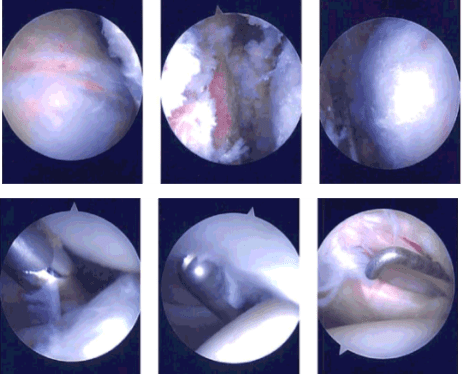

A posterior incision was given through the spot for the entry portal of the scope. The scope was entered into the glenohumeral joint and the glenohumeral joint was examined. There was labral tearing as well as articular site rotator cuff tearing. Debridement was performed using a shaver. Biceps were intact.

The subscapularis tendon as well as Inferior glenohumeral ligament and superior glenohumeral ligament were intact. There were grade 1 to grade 2 degenerative glenoid chondral changes using a shaver. Now, the scope was entered into the subacromial area where subacromial bursitis was present.

Shaver was used to decompress the subacromial region and bursectomy was performed. Acromial spurring and type 2 acromion were found. A burr was used to do the acromioplasty. The AC joint was found to be intact and no inflammation was found. The final pictures were taken.

Intraoperative Arthroscopy Images